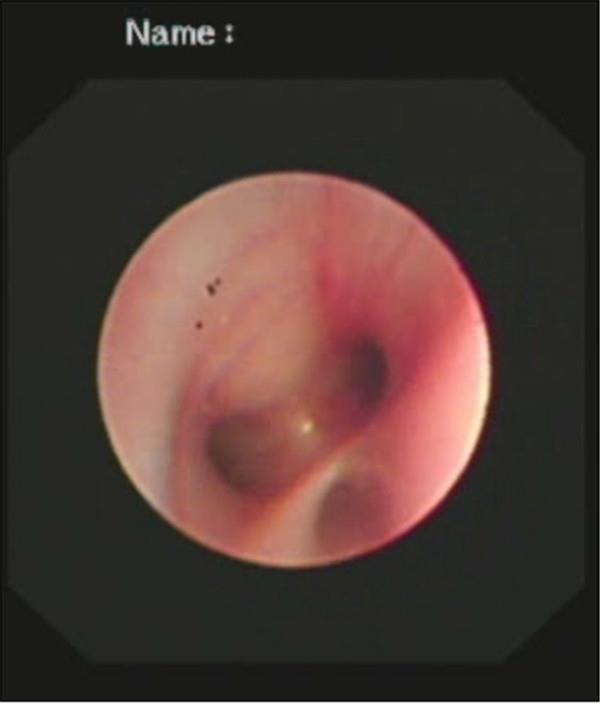

支气管镜检查中

检查中气道内情景